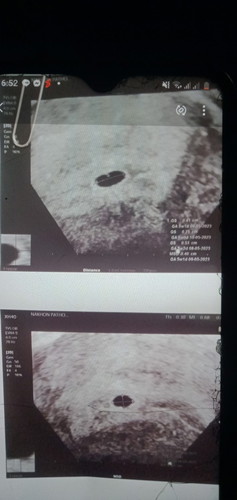

เรานับได้4สัปดา แต่หมอซาวได้5สัปดาค่ะ ผลซาวมีแบบนี้พอมีหวังไหมค่ะ

5wยังมีหวังค่ะ น้องอาจจะยังเล็กมากเลยไม่เจอตัว แต่ถ้านัดหน้าไม่เจออีกก็ท้องลมค่ะ

ของเราก็ 5 สัปดาห์ ไม่เจอน้องเหมือนกันค่ะ